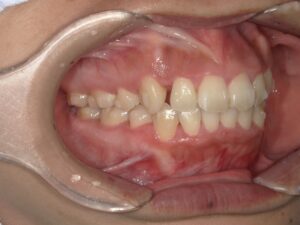

以下にコンピュータシュミレーションの最終予想を示します。

【治療終了シュミレーション】

このように、当院ではマウスピース矯正にてここまでの治療が可能です。